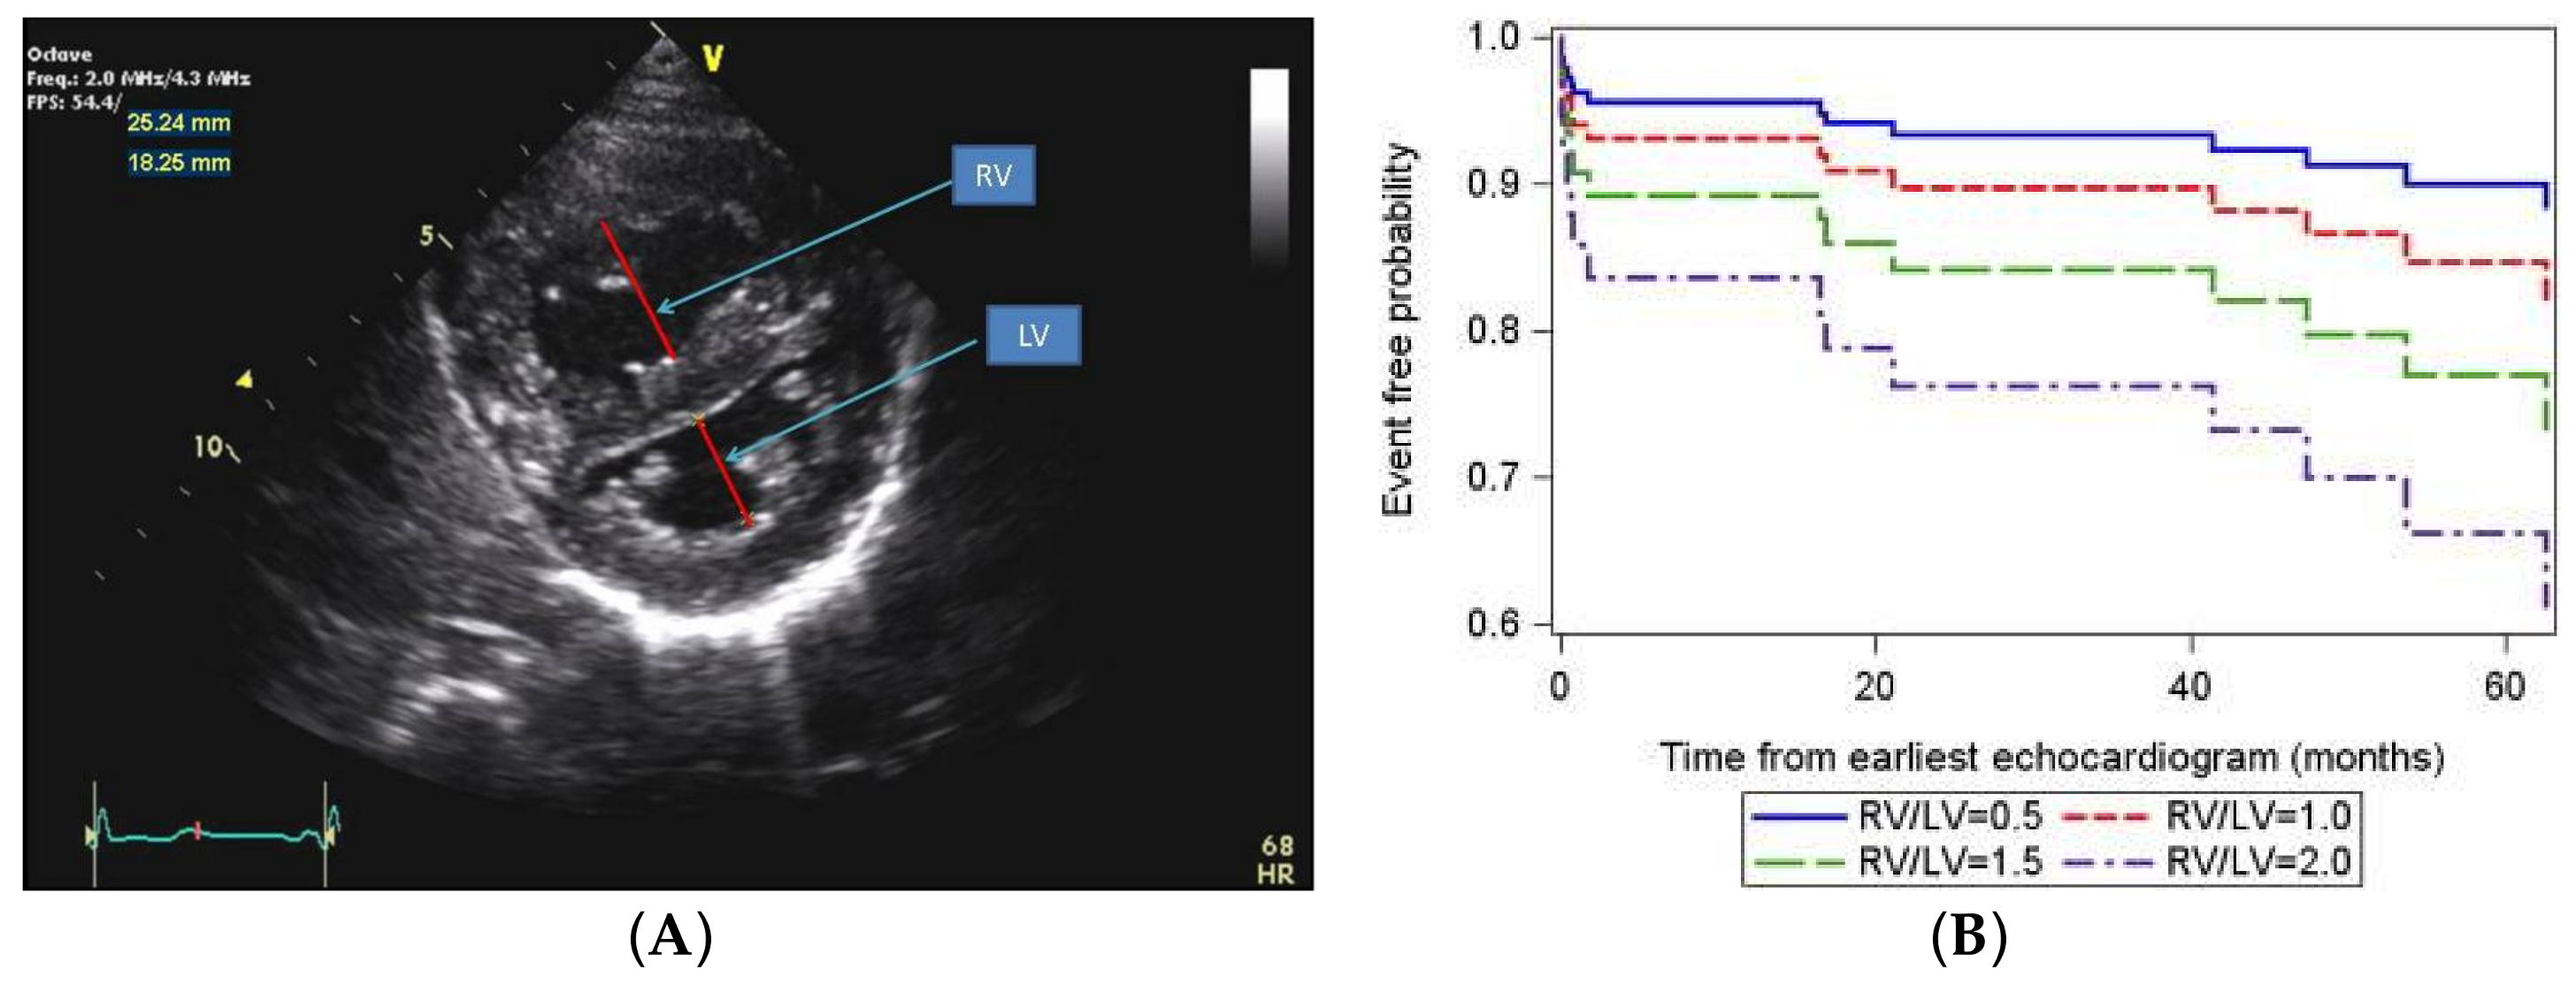

- Jone, P.N.; Hinzman, J.; Wagner, B.D.; Ivy, D.D.; Younoszai, A. Right ventricular to left ventricular diameter ratio at end-systole in evaluating outcomes in children with pulmonary hypertension. J. Am. Soc. Echocardiogr. 2014, 27, 172–178. [Google Scholar] [CrossRef] [PubMed]